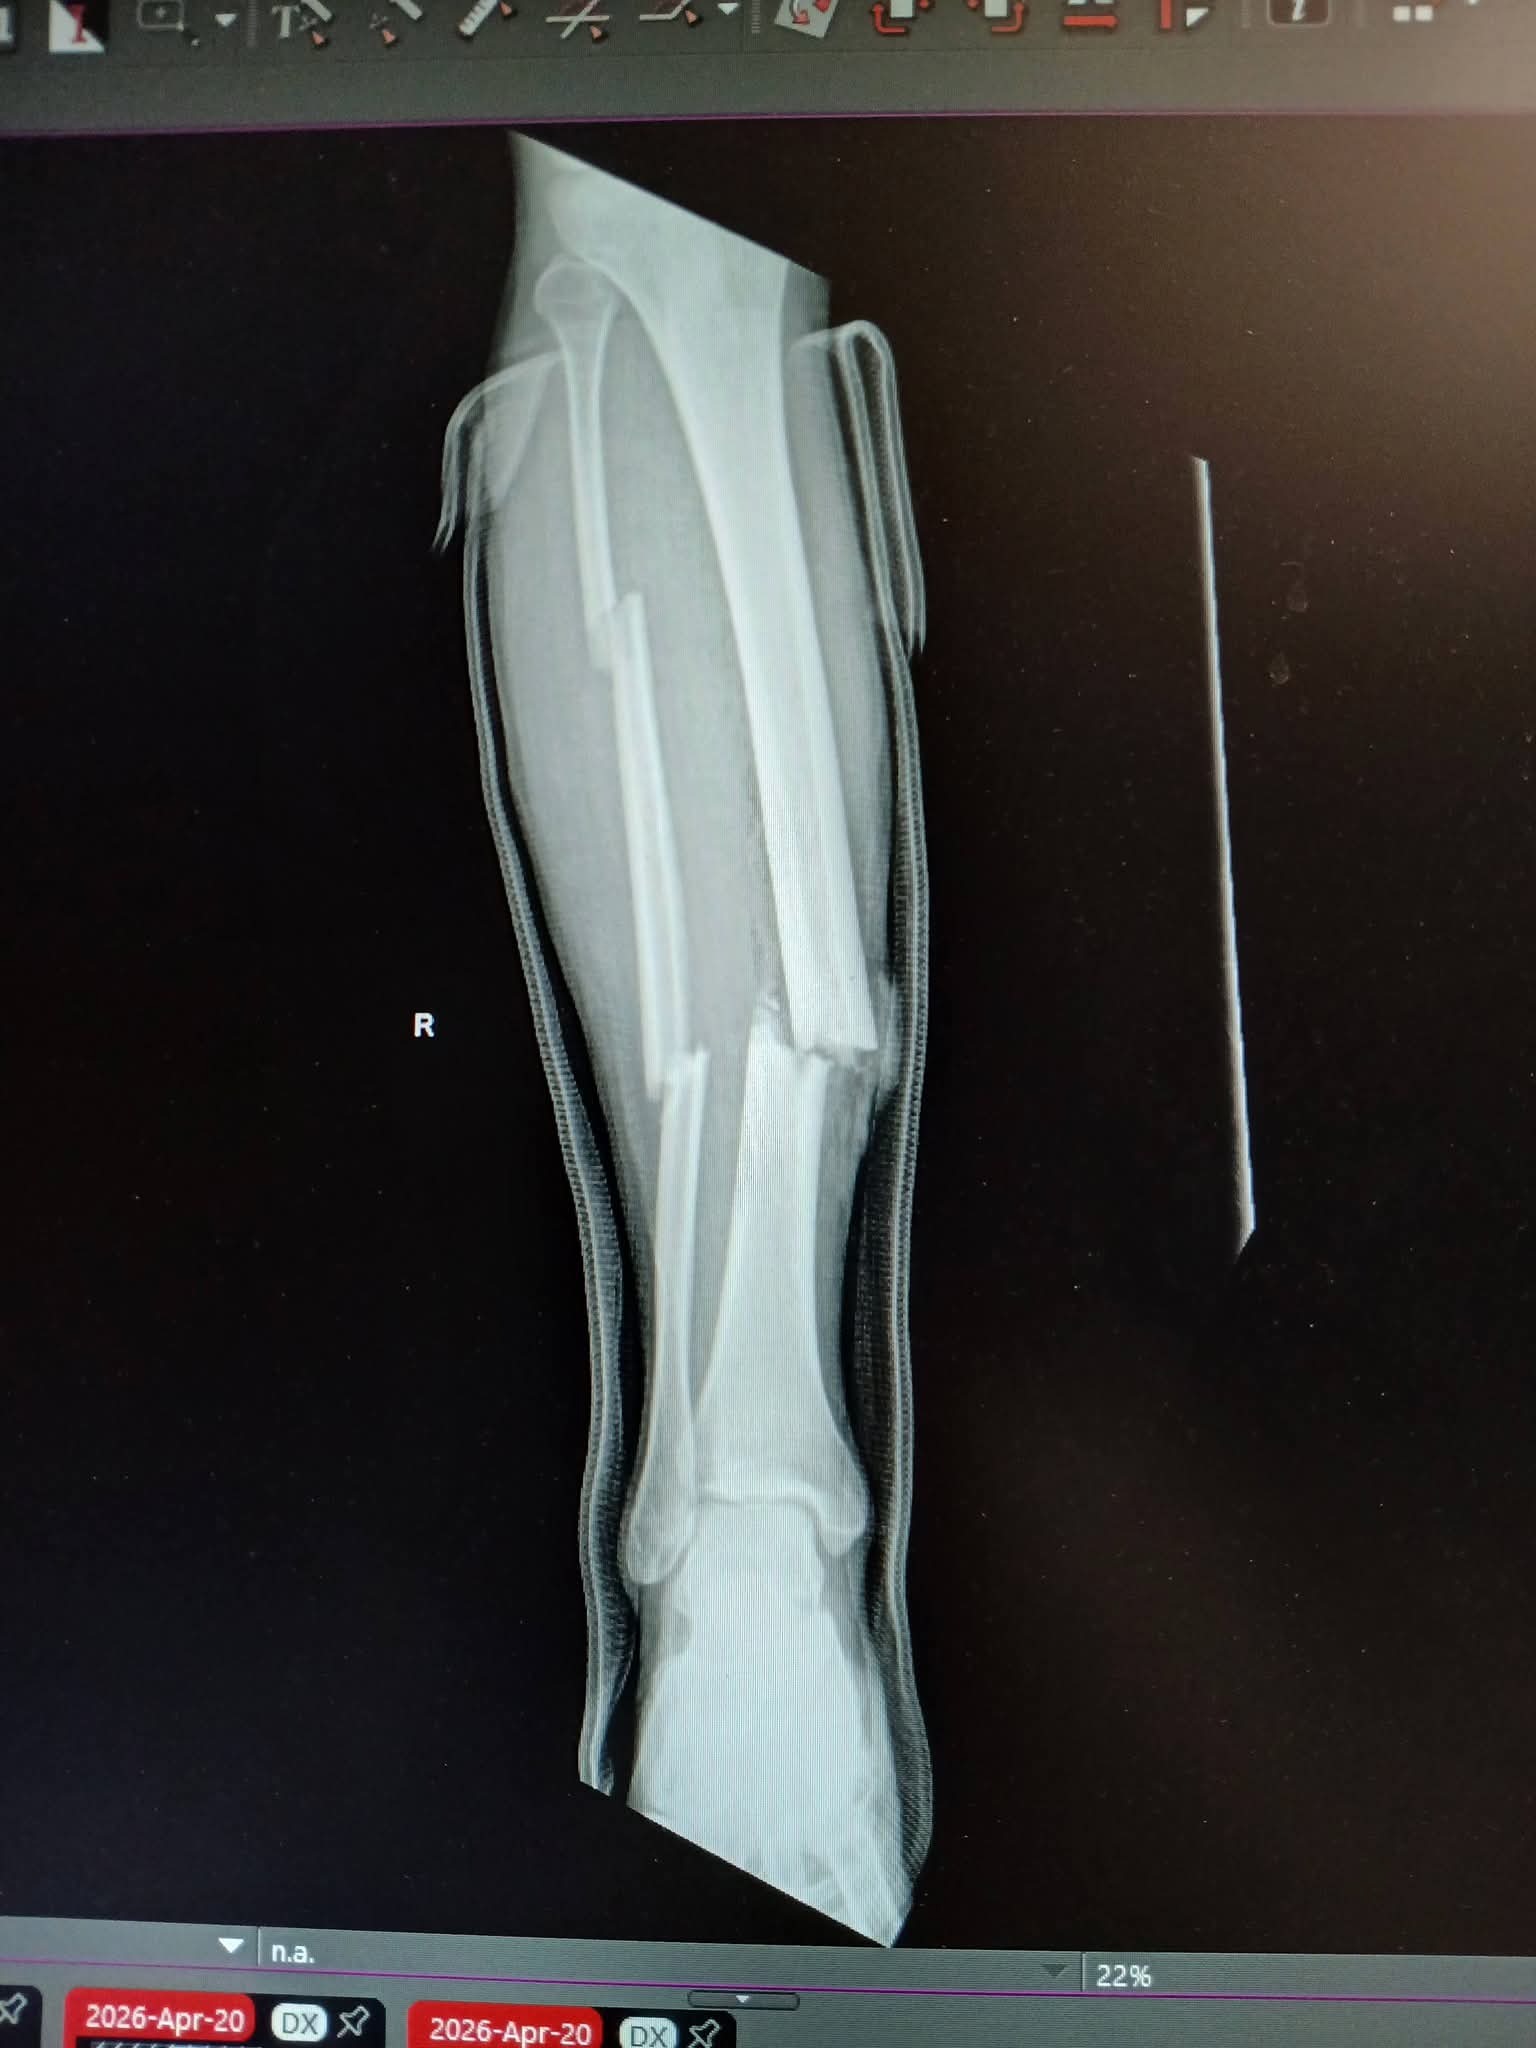

As some may have already heard, my boyfriend Nat was in a horrible motorcycle accident on Monday April 20th. He is going to have a long road to recovery with his leg broken in three places, a fractured rib, small fracture in his spine, a fractured wrist, abrasions on his lungs, and an AC ligament tear in his shoulder and rotator cuff. He has already been through one surgery on his leg, with a possible future surgery depending on how everything heals, as it is considered a high risk recovery and can have complications.